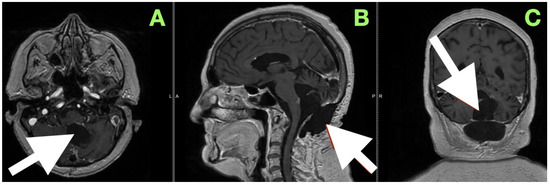

An immediate postoperative MRI (Figure 4) was performed to assess the resection extent and surgical purpose. Multiplanar T1-weighted sequences showed a sharply demarcated postoperative cavity; the fourth ventricle had expanded, all cerebrospinal fluid paths were unobstructed, and there was no abnormal enhancement seen. The imaging findings served as direct visual proof for the intraoperative aims, namely, decompression of the brainstem, anatomical re-establishment of the cisterns, and maintenance of surrounding neurovascular structures. No perilesional edema and no hemorrhagic debris support the use of the “stay-at-anatomy” dissection approach. Near-total resection with a midline suboccipital telovelar approach accomplished complete decompression, anatomical restoration, and preservation of all appropriate neurovascular structures. Immediate postoperative MRI demonstrated no residual mass effect or abnormal enhancement, with no imaging assessment of keratinaceous content, despite the fact that there was microbiologically adherent capsular remainder on the ventricular floor that was purposefully left intact.

A magnetic resonance image performed at this time (Figure 6) sought to provide an objective confirmation of surgical and clinical impressions. The axial T1-weighted post-contrast image (Figure 5A) demonstrated a sharply marginated, extra-axial postoperative cavity occupying the midline posterior fossa, with preservation of surrounding parenchymal architecture and no pathologic enhancement to suggest residual epidermoid tissue. There was no gliotic signal change or loss of regional volume, and the normal folial pattern of both cerebellar hemispheres was intact. The sagittal post-contrast T1-weighted image (Figure 5B) demonstrated a fourth ventricle in appropriate anatomical alignments, with unobstructed continuity between the aqueduct of Sylvius, the ventricular outlet foramina, and the cerebellomedullary cistern. The relationships between the cerebellar vermis, brainstem, and dorsal medulla displayed anatomical preservation, with no features suggestive of postoperative adhesive arachnoiditis or CSF flow obstruction.

Figure 4. Immediate postoperative MRI. (A) Axial, (B) sagittal, and (C) coronal T1-weighted images show a postoperative cavity with complete re-expansion of the fourth ventricle and patent CSF pathways (white arrows). No abnormal enhancement or diffusion-restricted focus is present, confirming gross total resection and restoration of posterior fossa anatomy.